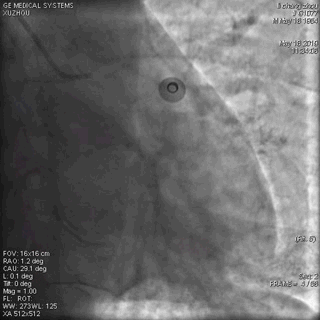

正常,冠脉造影正常。

(左冠脉造影2)